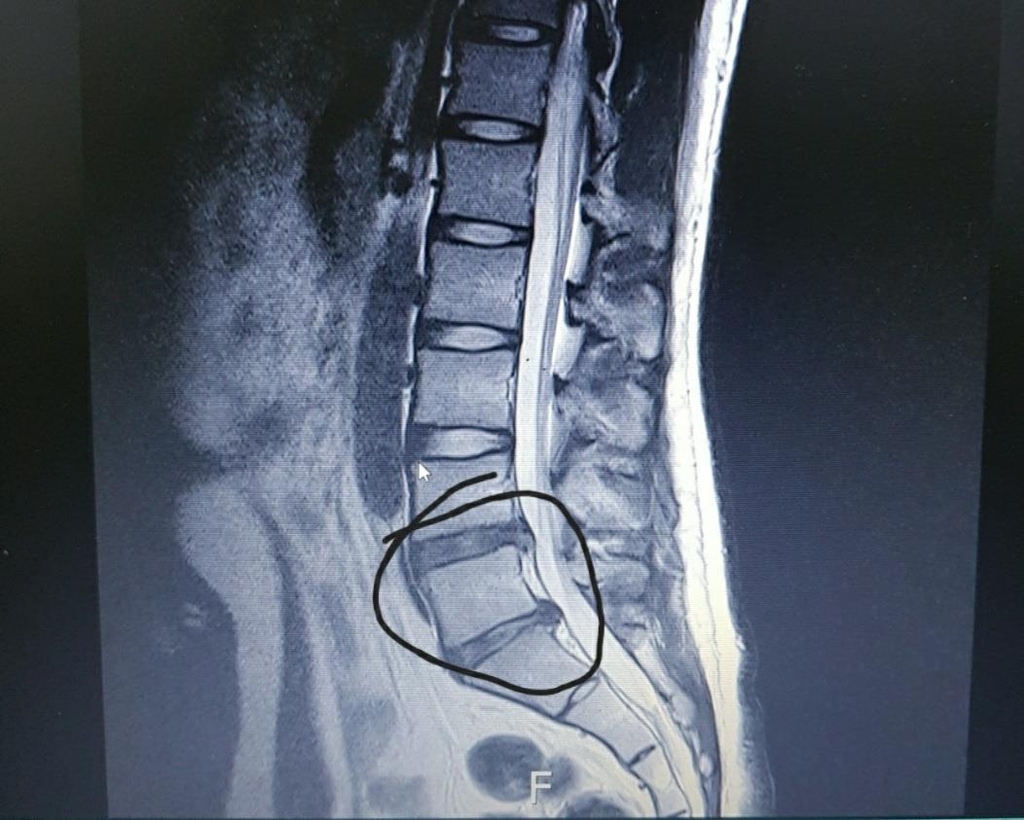

허리 협착증은 주로 노화에 따른 퇴행성 변화, 유전적 요인, 그리고 과도한 운동 등 다양한 원인으로 발생합니다. 허리의 디스크가 변형되거나 척추관이 좁아짐으로써 신경이 압박받고, 이는 심한 통증으로 이어질 수 있습니다.